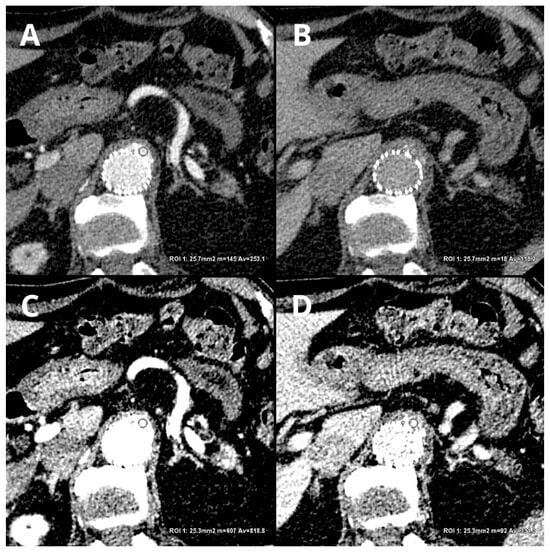

- Kazimierczak, W.; Kazimierczak, N.; Lemanowicz, A.; Nowak, E.; Migdalski, A.; Jawien, A.; Jankowski, T.; Serafin, Z. Improved Detection of Endoleaks in Virtual Monoenergetic Images in Dual-Energy CT Angiography Following EVAR. Acad. Radiol. 2023, 30, 2813–2824. [Google Scholar] [CrossRef]

- Maturen, K.E.; Kaza, R.K.; Liu, P.S.; Quint, L.E.; Khalatbari, S.H.; Platt, J.F. “Sweet spot” for endoleak detection: Optimizing contrast to noise using low kev reconstructions from fast-switch kVp dual-energy CT. J. Comput. Assist. Tomogr. 2012, 36, 83–87. [Google Scholar] [CrossRef] [PubMed]

- Martin, S.S.; Wichmann, J.L.; Weyer, H.; Scholtz, J.-E.; Leithner, D.; Spandorfer, A.; Bodelle, B.; Jacobi, V.; Vogl, T.J.; Albrecht, M.H. Endoleaks after endovascular aortic aneurysm repair: Improved detection with noise-optimized virtual monoenergetic dual-energy CT. Eur. J. Radiol. 2017, 94, 125–132. [Google Scholar] [CrossRef]